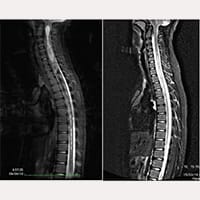

Obrazy RM Melanie

Przed zabiegiem SFT

Po zabiegu SFT